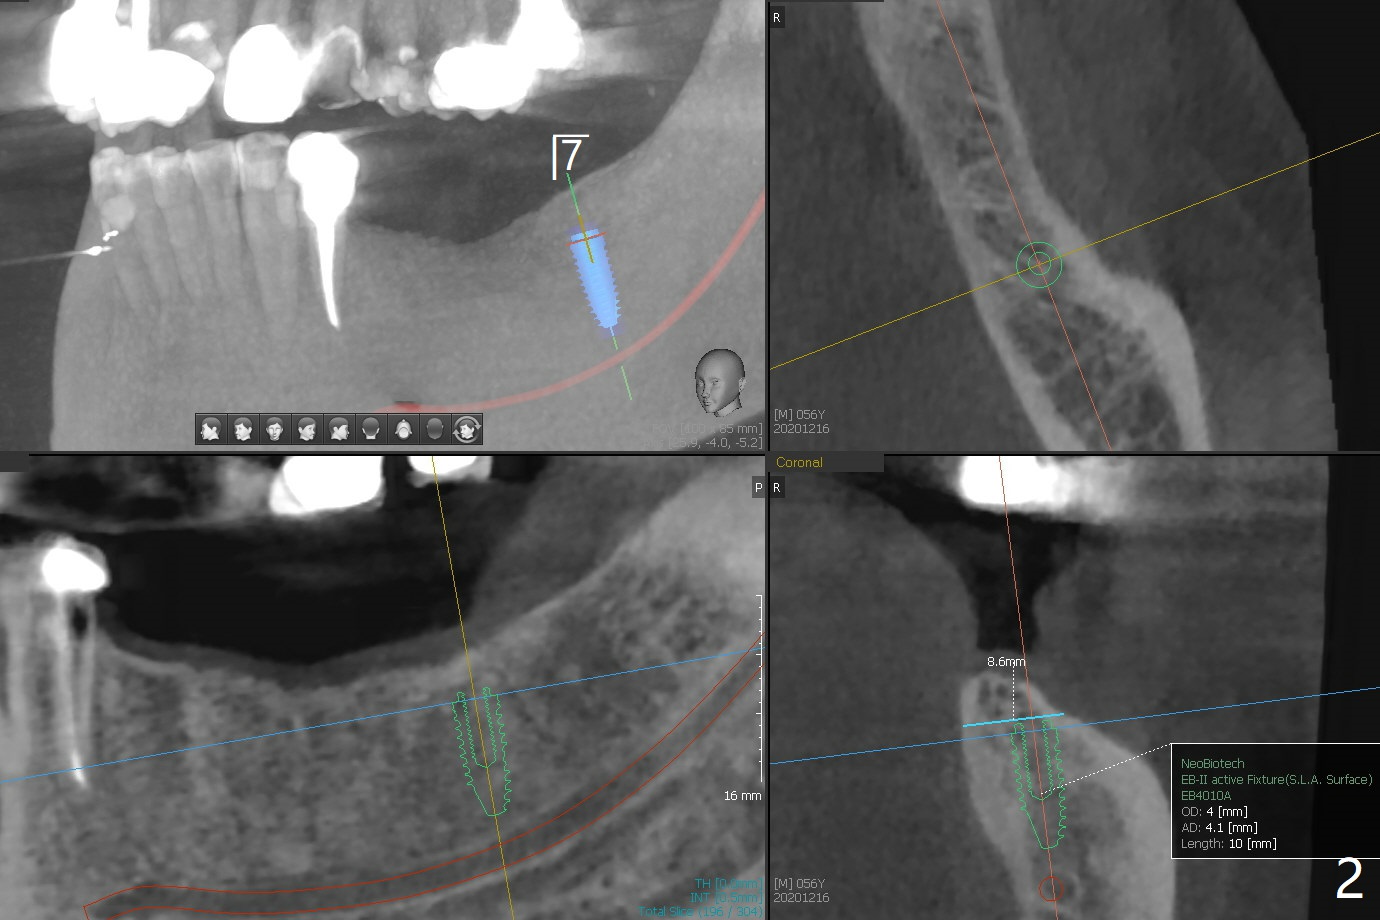

56岁男下颌可弯曲局部义齿(Valplast)靠托牙胶水固定,造成左下2远中颈部龋齿,后者修复后(图一),考虑在下7种植(图二,三),放置球帽基台固定义齿,改善口腔菌群。